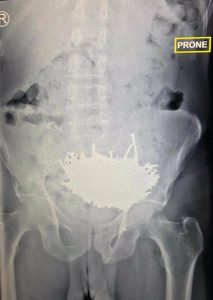

بالصور استخراج 230 مسمارًا من بطن مريض

أعلن فريق طبي سعودي إجراء جراحة ناجحة لاستخراج 230 مسمارًا، وقطع زجاج من بطن مريض، بلعها جراء إصابته بحالة نفسية. وقال الحساب الرسمي لمديرية الشؤون الصحية بمحافظة جدة السعودية، في تغريدة عبر تويتر: “أسهم بفضل الله تدخل طبي ناجح في إنقاذ حياة مريض بمستشفى شرق جدة، عبر استخراج 230 مسمارًا وقطع زجاج من بطنه”. وأضاف الحساب أن المريض كان يعاني آلامًا وانتفاخًا في البطن، وقد أظهرت الفحوصات الإكلينيكية والإشعاعية وجود عدد كبير من المسامير داخل معدة المريض